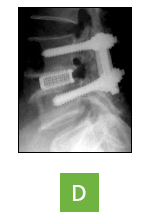

ôÃß À¯ÇÕ¼ú / ±â±â °íÁ¤¼ú

ôÃß°íÁ¤¼úÀº ôÃßÀÇ ¿Ü»óÀ̳ª ÅðÇ༺ º¯¼º, ¼ö¼ú ÈÄ ÈÄÀ¯Áõ, Á¾¾ç, ¿°Áõ, ¼±Ãµ¼º ±âÇü µî ôÃßÀÇ ±¸Á¶Àû ÀÌ»óÀ» Àç°ÇÇÏ´Â ¼ö¼ú¹ýÀÔ´Ï´Ù. 8~10cm Á¤µµÀÇ Àý°³¸¦ ÇÊ¿ä·Î Çϸç, Àΰøµð½ºÅ©³ª ³ª»ç¸øÀ» »ç¿ëÇØ ôÃߺÐÀýÀÌ Èçµé·Á ¹Ì²ô·¯Áö´Â °ÍÀ» ¸·°í, °íÁ¤µÈ ºÎÀ§°¡ ¸ö¹«°Ô¸¦ ÃÖ´ë·Î ¹ÞÃÄ ¾ÈÁ¤µÇ°Ô ÇØÁÝ´Ï´Ù.

µð½ºÅ© ¸¶µð¸¦ ±»È÷´Â ¼ö¼ú

- A : µ¹ÃâµÈ µð½ºÅ©¸¦ Á¦°ÅÇϸé

- B : ôÃß»À°¡ ºÒ¾ÈÀüÇØÁú ¼ö ÀÖ´Ù.

- C : À̸¦ ¿¹¹æÇϱâ À§ÇØ À§, ¾Æ·¡ ôÃß»À¸¦ ±»Çô ÁÖ´Â À¯ÇÕ¼úÀ» ½ÃÇàÇÑ´Ù.

- D : ôÃß À¯ÇÕ¼úÀ» º¸¿©ÁÖ´Â ¿¢½º·¹ÀÌ »çÁø

ÀåÁ¡

- ôÃ߸¦ °ß°íÇÏ°Ô °íÁ¤ÇØ ¾ÈÁ¤¼ºÀ» ÁÝ´Ï´Ù.

- ÁÙ¾îµç µð½ºÅ©ÀÇ ³ôÀ̵µ º¹¿øÇØ ½Å°æÀÌ ³ª°¡´Â Ãß°£°øÀ» È®ÀåÇØÁÖ´Â È¿°ú°¡ ÀÖ½À´Ï´Ù.

- ¼ö¼ú ÈÄ Áï°¢ÀûÀÎ ÅëÁõÇØ°áÀÌ °¡´ÉÇÕ´Ï´Ù.

- Àü¹æÀüÀ§Áõ°ú °°ÀÌ Ã´Ãß ¸¶µð°¡ ¾î±ß³ªÀÖ´Â °æ¿ì Á¦ À§Ä¡·Î µ¹¾Æ¿Ã ¼ö ÀÖ°Ô ÇØÁÝ´Ï´Ù.

- º´ÀÌ Àִ ôÃ߸¶µð¸¦ À¯ÇÕ½ÃÅ´À¸·Î¼ º´ÀÌ ´Ù½Ã Àç¹ß ÇÒ °¡´É¼ºÀ» Â÷´Ü½Ãŵ´Ï´Ù.